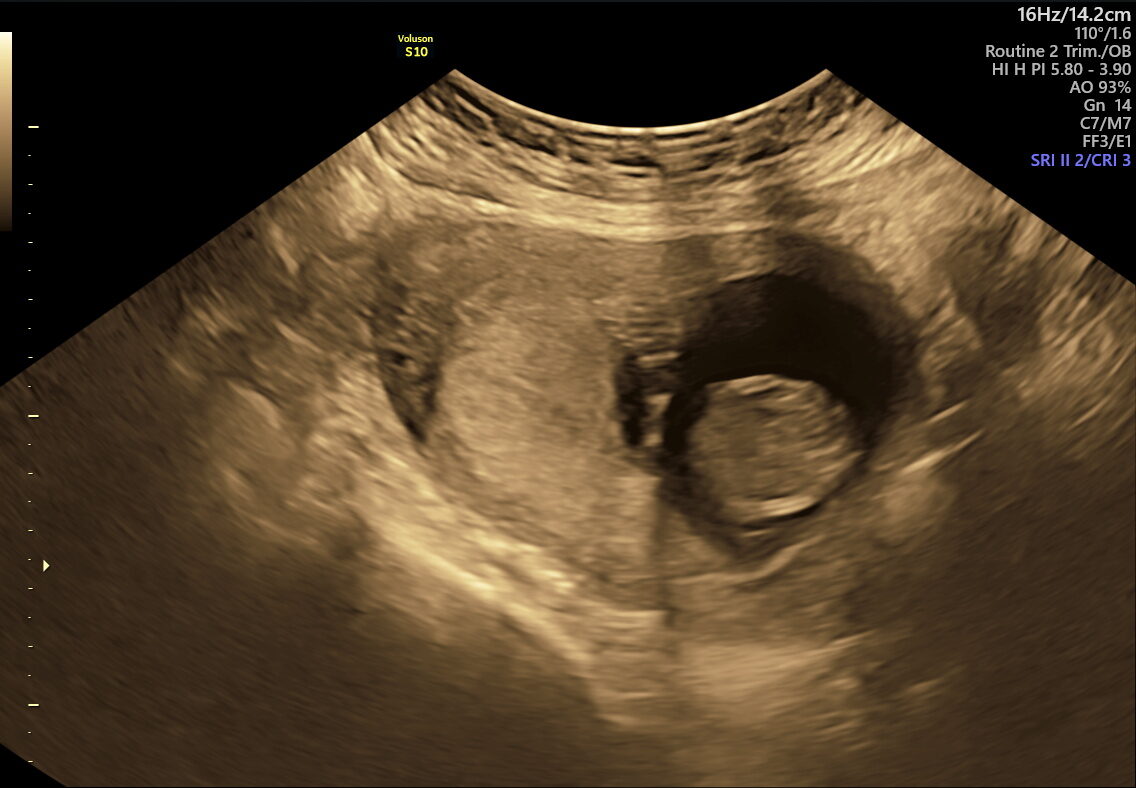

CVS is an early genetic test done between 10–13 weeks of pregnancy. A tiny sample of placental tissue (chorionic villi) is taken to analyze the baby’s chromosomes. CVS provides early answers for families at risk of genetic disorders or who have had abnormal screening results. Unlike screening tests that estimate risk, CVS provides clear, laboratory-confirmed answers. It is performed in the first trimester, making it one of the earliest opportunities for definitive genetic diagnosis during pregnancy.

CVS is typically performed between 10–13 weeks of pregnancy.

- High-resolution ultrasound guidance ensures accurate sampling and minimal risk